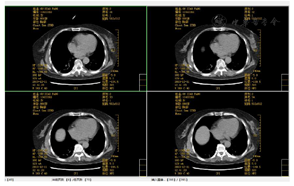

2019年8月3日急诊头颅CT提示:右侧脑出血,伴蛛血(图1)。2019年11月27胸日部CT提示:肺部感染,部分实变(图2、图3)。呼吸功能评估:胸廓活动度明显下降,呼吸肌肌力和耐力下降,无自主咳嗽。绿染实验提示患者有误吸,无食道反流情况。吞咽功能评估:存在误吸,咳嗽力量欠佳,口腔运送能力差,吞咽启动明显延迟,咽缩肌无力,下颌运动受限。

4.治疗中期及拔管前功能评估:未吸氧,血氧饱和度正常范围,生命体征平稳。主动张口幅度1.5 cm,被动张口幅度2.5 cm,自主咳嗽能力正常、自主清嗓较稍减弱,咽反射正常,吞咽启动减慢,喉上抬范围1.0 cm,简易吞咽诱发试验正常。气切管固定稳妥,未见异常分泌物。经气切口通气,呼吸平稳;膈肌移动度及呼吸肌肌力和耐力正常。Brunnstrom运动功能评定:左上肢3期、左手3期、左下肢4期。左侧肢体浅感觉较对侧减退,左肘及左膝关节平面以下感觉减弱。颈部被动活动无明显受限。站立平衡1级及坐位平衡2级。完善吞咽造影检查:可进食1、2、3号食物,吞咽造影提示患者吞咽启动减慢,吞咽耐力部分下降(视频2)。拔管前辅助检查评估:(1)完善颈部CT未见颈部无软组织肿胀及呼吸道受压;(2)电子鼻咽喉镜未见气道狭窄,声门开放可(视频3);(3)未吸氧情况下血气分析未见明显异常,肺功能大致正常;(4)肺部CT(图4、图5)提示感染基本控制,炎症明显吸收,血感染指标正常;(5)连续堵管训练24 h,患者血氧饱和度及血气分析正常。